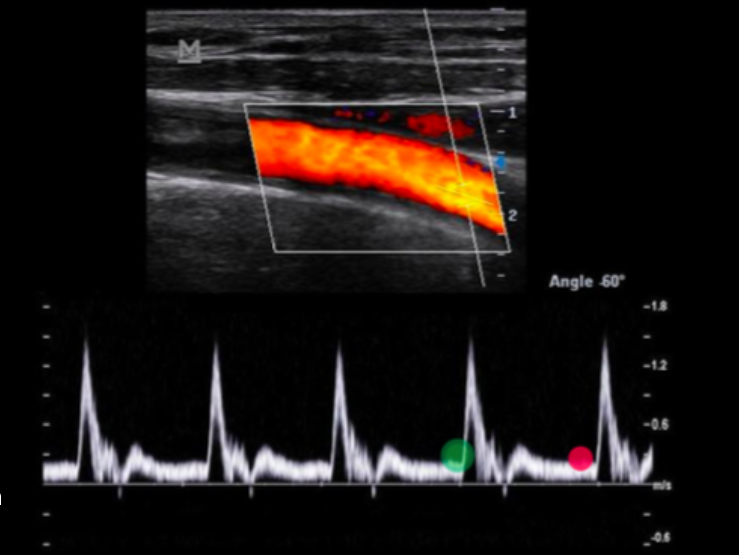

WHile scanning the carotid artery, you obtain a Doppler tracing and obtain the peak velocity. Before recording the image, you decrease the cursor angle from the last sample taken to make it more parallel to the flow and record the new image. How will this change affect the peak velocity displayed from the new sample?

a. no change unless stenosis is present

b. no change

c. increase

d. decrease

increase

What is being measured on the Doppler tracing?

a. resistive index

b. peak diastolic velocity

c. peak systolic velocity

d. end diastolic velocity

peak systolic velocity

Use your cursor to measure the end diastolic velocity of the third waveform. Use your mouse to position the cursor and click to set your answer.

(green)